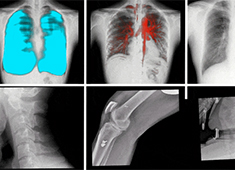

影響DR圖像質(zhì)量的因素有哪些方面

哪些因素會(huì)影響DR圖像質(zhì)量呢?普愛醫(yī)療歸納了以下幾大因素。當(dāng)前國產(chǎn)DR都尤其重視圖像后處理系統(tǒng)的升級(jí),如普愛醫(yī)療研發(fā)生產(chǎn)的多功能動(dòng)態(tài)DR(型號(hào):PLX8100),應(yīng)用了公司自主研發(fā)的組織均衡技術(shù),它是基于低灰度區(qū)擴(kuò)展到高...

百微米DR的臨床優(yōu)勢(shì):呈現(xiàn)更豐富的成像細(xì)節(jié)

目前市面上已經(jīng)開始漸漸流行“百微米DR”,百微米DR好在哪里,具有什么樣的臨床優(yōu)勢(shì)?以PERLOVE品牌的PLX8100為例,這是一款大尺寸的多功能動(dòng)態(tài)DR機(jī),搭載了高性能的百微米平板,4K*4K采集矩陣與100μm像素...